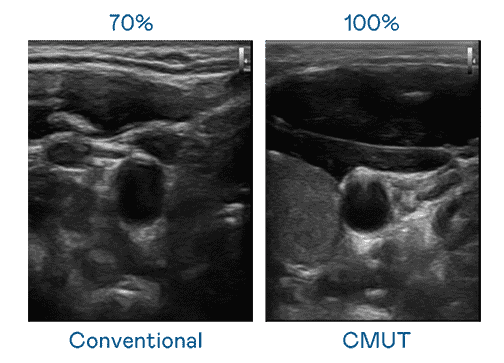

CMUT 技术是一种用电容式微机电元件来产生超音波讯号的技术。。。。与传统 PZT 压电式技术相比,,,CMUT 频宽增加 30%,,,更宽频的超音波讯号让影像解析度大幅提升,,,,是实现高影像品质医疗超音波扫描、、、促进精准医疗发展的关键技术。。。

大频宽带来超清晰影像

超音波影像的解析度高低,,,首先取决于探头能发出的讯号频宽。。28国际 CMUT 可提供高清晰的超音波讯号,,,提供高频宽、、高灵敏度、、、影像纹理细节更高的超音波影像,,协助医护人员缩短影像判读时间及利用精准的医疗影像进行诊断。。